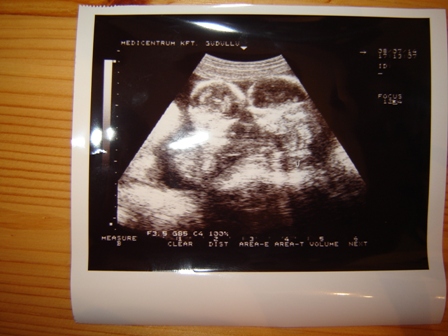

a Kistesók